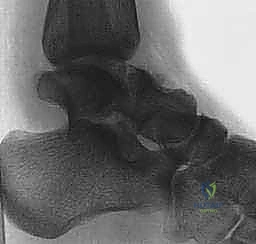

2. التصوير الإشعاعي (الأشعة السينية - X-rays)

هي الخطوة الأولى. تُطلب صور من زوايا متعددة:

* الرؤية الأمامية الخلفية (AP).

* الرؤية الجانبية (Lateral).

* رؤية الهاون (Mortise view).

* رؤية كانال (Canale View): وهي وضعية تصوير خاصة جداً لتقييم عنق الكاحل وتحديد درجة الإزاحة بدقة.

3. التصوير المقطعي المحوسب (CT Scan) - المعيار الذهبي

في عيادة الأستاذ الدكتور محمد هطيف، يُعتبر التصوير المقطعي المحوسب ثلاثي الأبعاد (3D CT Scan) إجراءً روتينياً وحتمياً لأي كسر في عظم الكاحل. توفر الأشعة المقطعية تفاصيل دقيقة للغاية عن خطوط الكسر، مدى التفتت (Comminution)، وحجم الإزاحة المفصلية التي لا يمكن رؤيتها بالأشعة السينية العادية. بناءً على هذه الصور، يقوم الدكتور هطيف ببناء استراتيجية الجراحة (أين سيفتح، ما نوع الشرائح والمسامير التي سيستخدمها، وكيف سيعيد بناء العظم).